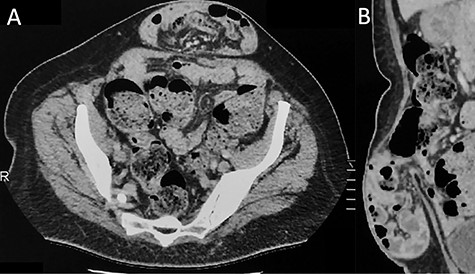

ALH is a peculiar type of interstitial parietal hernia of the anterior abdominal wall subdivided into three types [5] and more commonly identified in man, with a sex ratio difference of 12.5:1. One explanation is that more than a third of females don’t have a defined arcuate line, whereas most males do [6]. ALH rarely causes symptoms, as the hernia orifice is wide and can be easily mistaken as a Spigelian hernia on preoperative imaging that explains the number of cases only being diagnosed at laparoscopy [7]. Similarly, in our case, only the ventral hernia was clinically obvious and the bilateral ALHs were incidentally detected during laparoscopy. This reinforces the superiority of laparoscopy that allows us, alike in groin hernia surgery, to detect and simultaneously repair any coexistent defects [8]. Anecdotally, further re-examination of the preoperative CT-scan could probably reveal ascending protrusion of bowel between the right posterior rectus sheath and rectus muscle (Fig. 6).

Axial view of contrast-enhanced CT scan showing a small opening (>) with ascending protrusion of bowel between the posterior rectus sheath (black arrow) and the rectus muscle (white arrow).